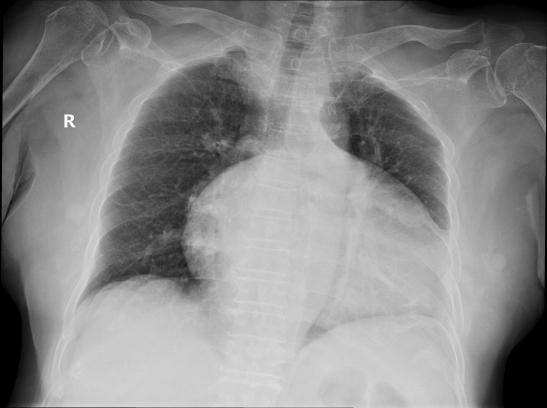

张奶奶的病榻前,厚厚的病历记录着棘手的病情:摔伤导致的骨折,叠加已至晚期的髋关节骨关节炎,关节软骨磨损殆尽,每走一步都像“骨头磨骨头”,夜间更是疼得无法入眠。更让人揪心的是,心脏彩超显示她患有三尖下移畸形并重度关闭不全,还合并重度肺动脉高压,右心房、右心室明显增大,心功能代偿能力极差。此前,张奶奶的家人曾带她到本市其他医院就诊,均因“考虑心肺功能较差”被拒绝手术治疗。就在一家人几乎要放弃时,朋友偶然提起,前海人寿韶关医院骨科在高龄高危患者微创治疗方面有丰富经验,一家人抱着最后一丝希望,来到我院骨科就诊。

“患者的心脏就像一个‘超负荷运转的老旧水泵’,任何手术创伤都可能引发心肺并发症,甚至危及生命。”主治医师宗金利回忆起初诊时的场景,语气凝重。传统髋关节置换手术需切断5块肌肉,出血量大、创伤明显,对张奶奶的心脏而言无疑是“致命负担”。但如果不手术,她将彻底丧失行走能力,生活质量急剧下降,甚至可能因长期卧床引发更多并发症。